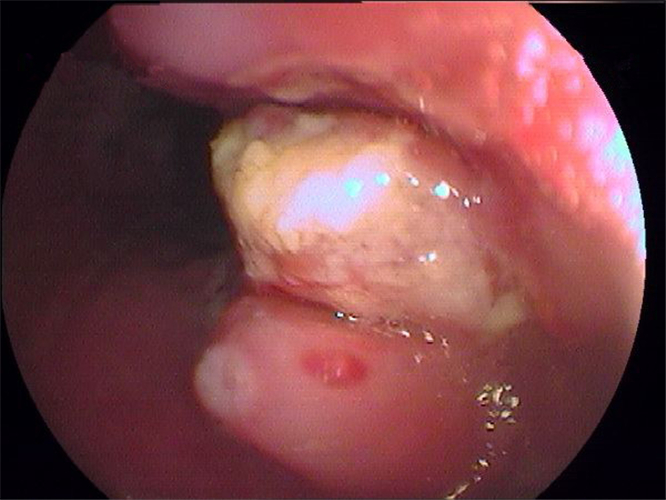

慢性胃炎圖片

慢性胃炎